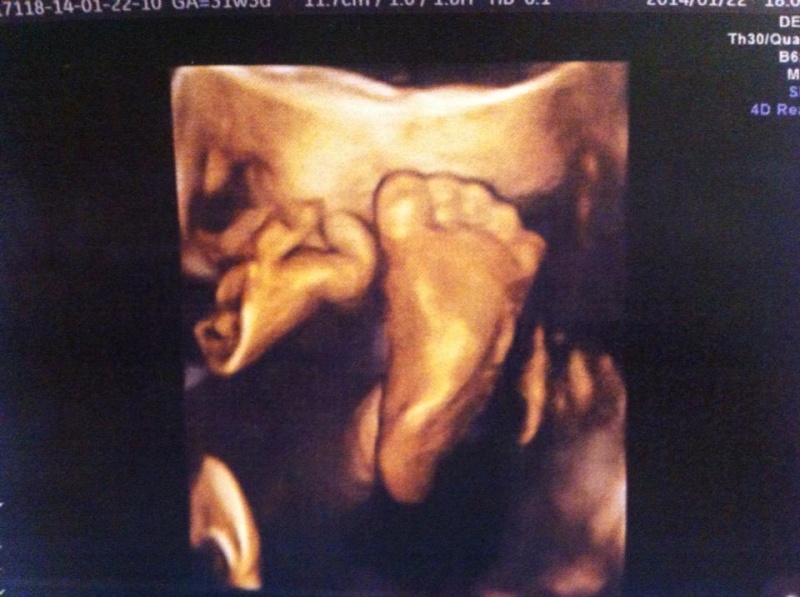

Bocs hogy itt ódázok hogyan vertük el a pénzt, de olyan boldog vagyok, hogy ennyi mindent beszereztünk, főleg hogy mostmár tényleg kezd nehézkes lenni minden. Nőtt a pocak is, és már nehezebben kapok levegőt, észrevettem, illetve csak tökegyenesen tudok ülni. A férjem lánya mindig rosszalkodik és nem hagy aludni..Ilyenkor a "te lányod" jelződ kapja szegény, mert este is már szinte kínzott több mint 1 órán át ugy rukapált, mocorgott hogy szinte fájt, én meg rettenet fáradt voltam, de nem hagyott..